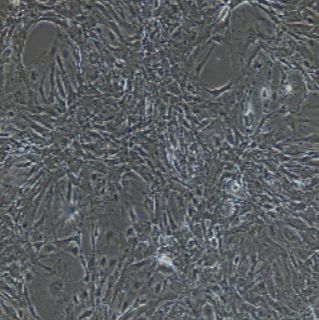

形态特性:圆形,多角形细胞

生长特性:贴壁培养

5) 细胞生长方式:圆形,多角形细胞,贴壁培养。